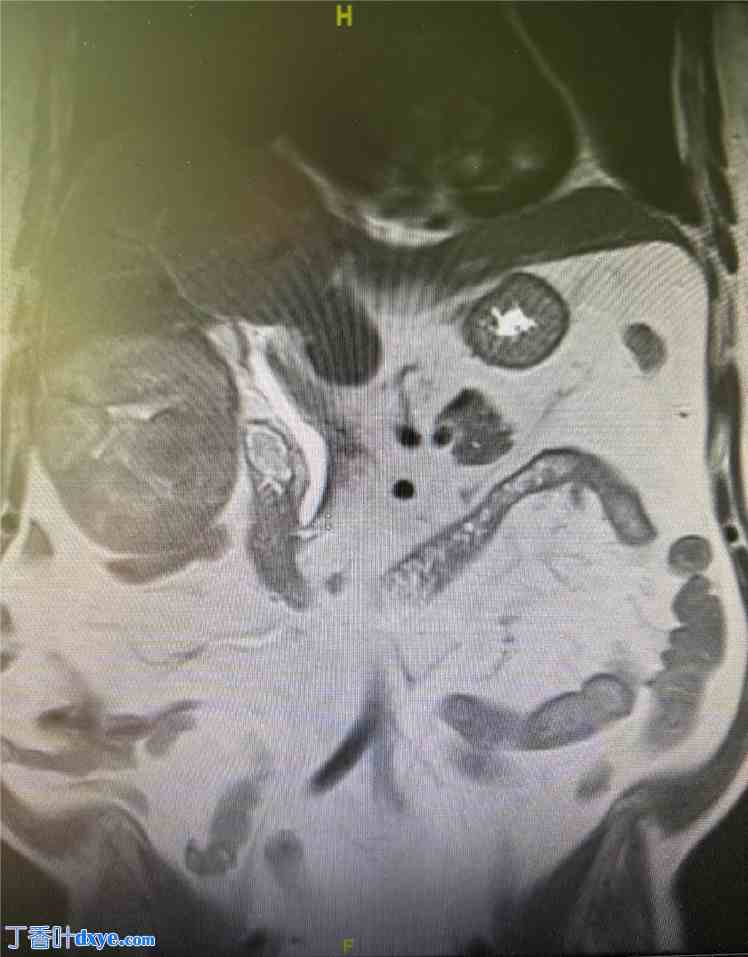

我曾亲身经历过一位患者,我曾对他使用这种方法,但失败了。患者是一位 66 岁的男性,没有慢性肝病的特征。他被诊断患有肝右叶肝细胞癌,肿瘤大小为 9.3 cm × 8.6 cm。肿瘤部分外生,累及肝5段和部分肝6段(图 1)。

图 1.

图片显示 9.3 cm × 8.6 cm 的肝细胞癌,部分外生,累及肝5段和部分肝6段。